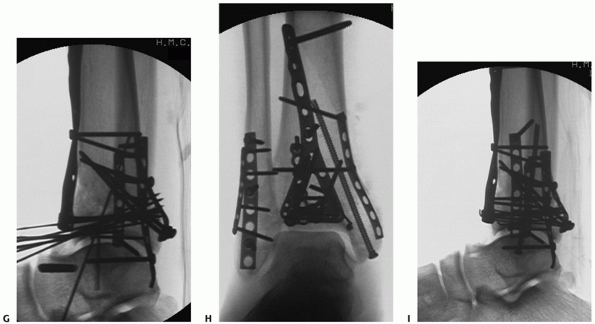

FIGURE 56-13 (continued) At the conclusion of fixation, the distal tibia was managed with spanning external fixation (G-I).

After resolution of soft tissue swelling, the remainder of the tibial plafond was reduced and stabilized using a modified anteromedial approach. (continues) |